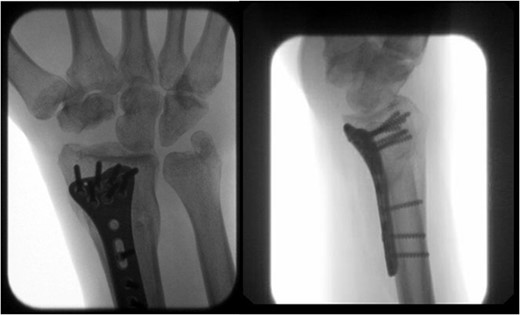

At 3-month postoperative follow-up, grip strength was 18 lbs on the right and 25 lbs on the left. Pinch strength was 9 lbs on the left and 7 lbs on the right. At 5-month follow-up, the patient was transporting himself using a wheelchair, and his wrist pain was well controlled. At 7-month follow-up, grip strength was improved to 30 lbs on the right and 45 lbs on the left; pinch strength was 3 lbs on the right and 8 lbs on the left. Right wrist motion demonstrated 40° of flexion, 20° of extension, and full unlimited pronosupination. Radiographs demonstrated a healed distal radius fracture with no signs of arthrosis at the new radiocarpal joint (Fig. 4). At 1-year follow-up, the patient continued to progress functionally with no new complaints of pain. At 2-year follow up, the patient’s Disabilities of the Arm, Shoulder, and Hand score was 35.83.

AP and lateral views at 7-month follow-up demonstrating a healed right distal radius fracture without arthrosis at the new radiocarpal joint.